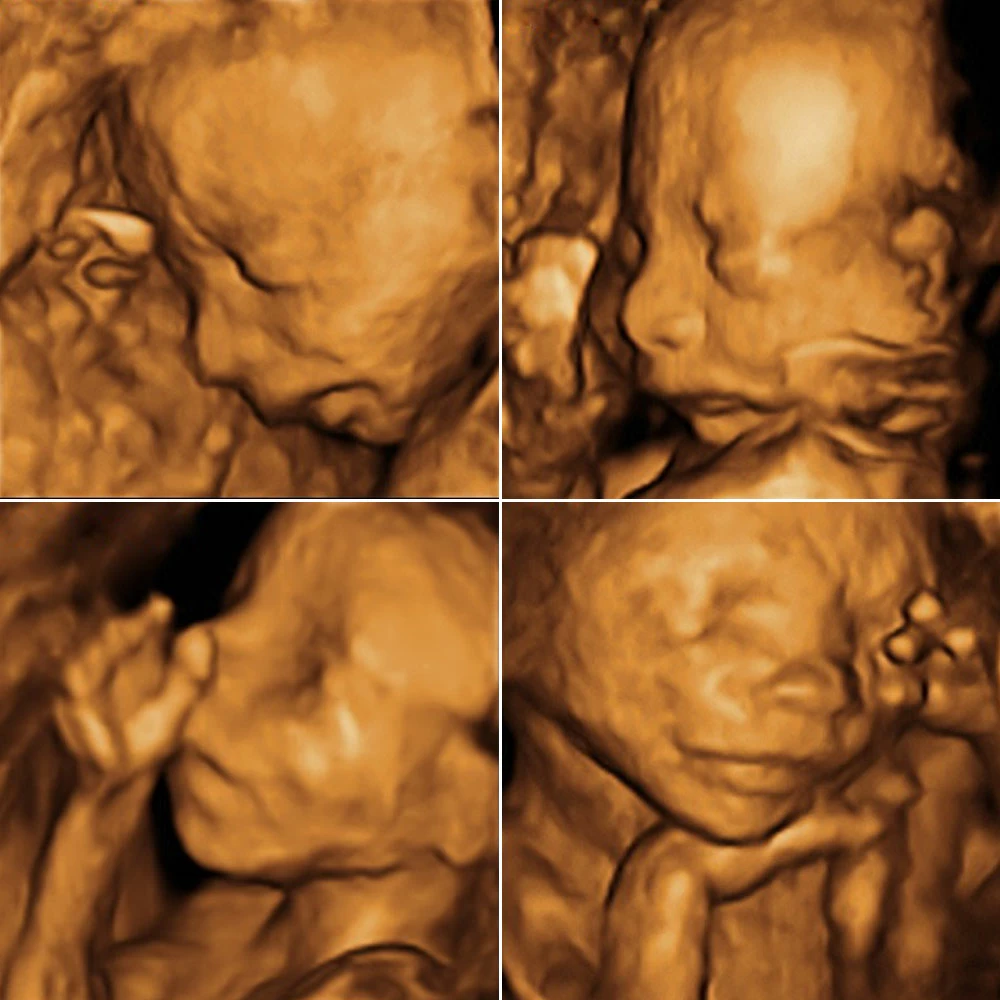

Неделя № 22

На 22 неделе размеры плода увеличиваются до 28 см, вес – до 450-500 грамм. Размеры головки становятся пропорциональны туловищу и конечностям. Ноги практически все время находятся в согнутом состоянии.

Полностью сформирован позвоночник плода: он имеет все позвонки, связки и суставы. Продолжается процесс укрепления костей.

Совершенствуется нервная система плода: головной мозг содержит уже все нервные клетки (нейроны) и имеет массу около 100 грамм. Ребенок начинает интересоваться своим телом: ощупывает свое лицо, руки, ноги, наклоняет голову, подносит пальцы ко рту.